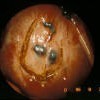

Endometriosis lesions*